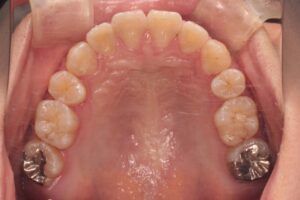

治療結果

歯並びもよくなりましたが、側貌の改善も顕著でした。